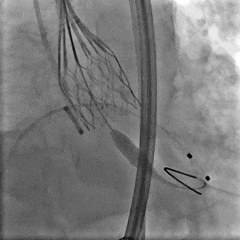

根部造影

27瓣膜0位释放至全展开

全展开造影,瓣膜位置可,形态稳定

脱钩后造影,瓣膜0位,无反流

多体位确认,瓣膜稳定